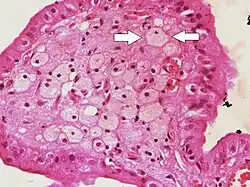

Vesicular mole | Micrograph of vesicular mole showing oedematous chorionic villus with circumferential proliferation of trophoblasts. | Category: Histopathology of chorionic villi | chorionic villi |